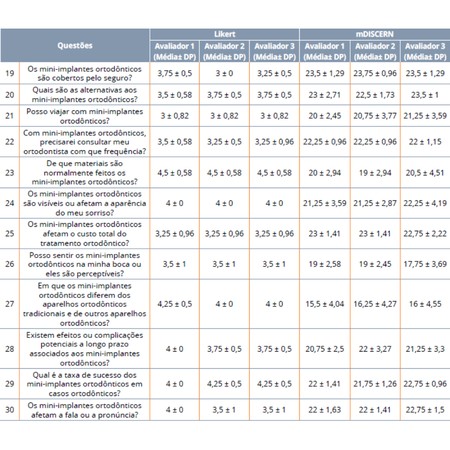

Introdução: Na presente era da Inteligência Artificial (IA), a concorrência crescente aumentou significativamente o poder dos chatbots de IA, que foram integrados a diversas áreas, incluindo a Ortodontia. Eles podem ser uma boa opção para esclarecer dúvidas antes ou durante o tratamento, pois são facilmente acessíveis aos pacientes. No entanto, sua confiabilidade ainda é uma preocupação. Mini-implantes, ou Dispositivos de Ancoragem Temporária (DATs), frequentemente usados...

Introduction: In this era of artificial intelligence, the increasing competition has significantly enhanced the power of AI chatbots, which have been integrated into various fields, including orthodontics. They can be a good option for enlightening topics of curiosity before or during treatment, as they are easily accessible by patients. However, their reliability remains a concern. Miniscrews, or Temporary Anchorage Devices (TADs), frequently used during orthodontic treatments, are among...